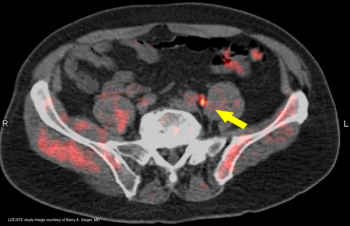

Findings from 18-fluciclovine (Axumin) positron emission tomography/computed tomography imaging had a major impact on management decisions for men with biochemical recurrence of prostate cancer.